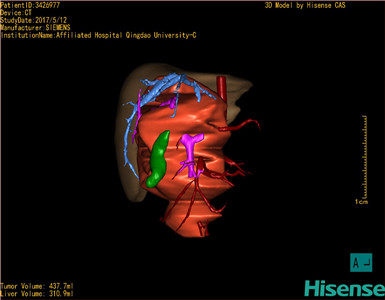

CT结果输入海信CAS系统后行3D重建及手术规划后,肿瘤位于右肾上腺区并周围淋巴结肿大,与血管关系紧密,建议化疗,静脉高营养、全量补液及对症支持治疗,患儿恢复良好,伤口无渗血渗液,无红肿疼痛,于2017-5-16出院。

术前三维重建:

重建图片